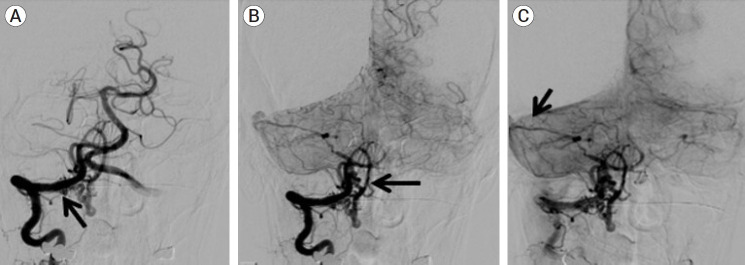

摘要椎动脉硬膜动静脉瘘是一种罕见的疾病。我们报告了一位有晕厥前症状的患者,发现在脑膜后动脉和流入乙状窦的皮质静脉之间有VADAVF。患者最初接受了手术干预,但未能消除分流。使用分流器的血管内治疗提供了明确的分流断开。

Vertebral artery dural arteriovenous fistulae (VADAVF) are a rare entity. We present a patient who experienced pre-syncopal symptoms and was found to have a VADAVF between the posterior meningeal artery and a cortical vein draining into the sigmoid sinus. The patient initially underwent surgical intervention, which failed to obliterate the shunt. Endovascular treatment with use of a flow diverter provided definitive disconnection of the shunt.